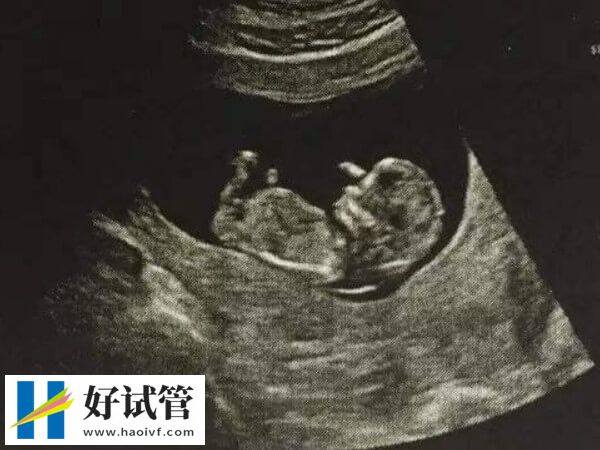

- 5. 子宫停止增大:当胚胎停育后,体内的激素水平会发生变化,导致子宫不再继续增大。这种情况可以通过超声波检查来确认,表现为子宫大小与怀孕周数不符。